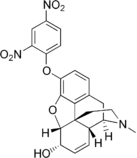

- 2,4-Dinitrophenylmorphine

2,4-Dinitrophenylmorphine 2,4-Dinitrophenylmorphine |